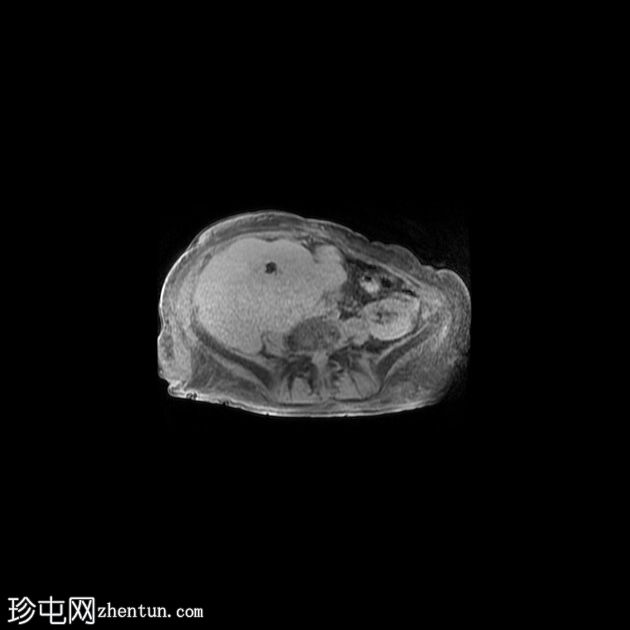

右髂窝移植肾不规则且受压,肾周可见巨大分叶状肿块,T2呈高信号,并进行性不均匀强化。这是黏液样变性的典型表现。

为确诊肾周脂肪黏液样假瘤,进行了活检。该假瘤是慢性肾脏炎症背景下的良性反应性病变,并非真正的肿瘤。最终行移植肾切除术,切除标本大小为26 x 18 x 12 cm,再次证实了诊断。

该过程反映了肾周脂肪组织的黏液样变性和纤维增生,本质上是指肾周脂肪中含有水肿的、富含黏蛋白的/黏液样结缔组织,具有典型的CT和MRI表现(T2高信号,轻度/中度强化)。鉴别诊断可能包括脂肪肉瘤以及与慢性炎症/黄色肉芽肿感染相关的并发症。